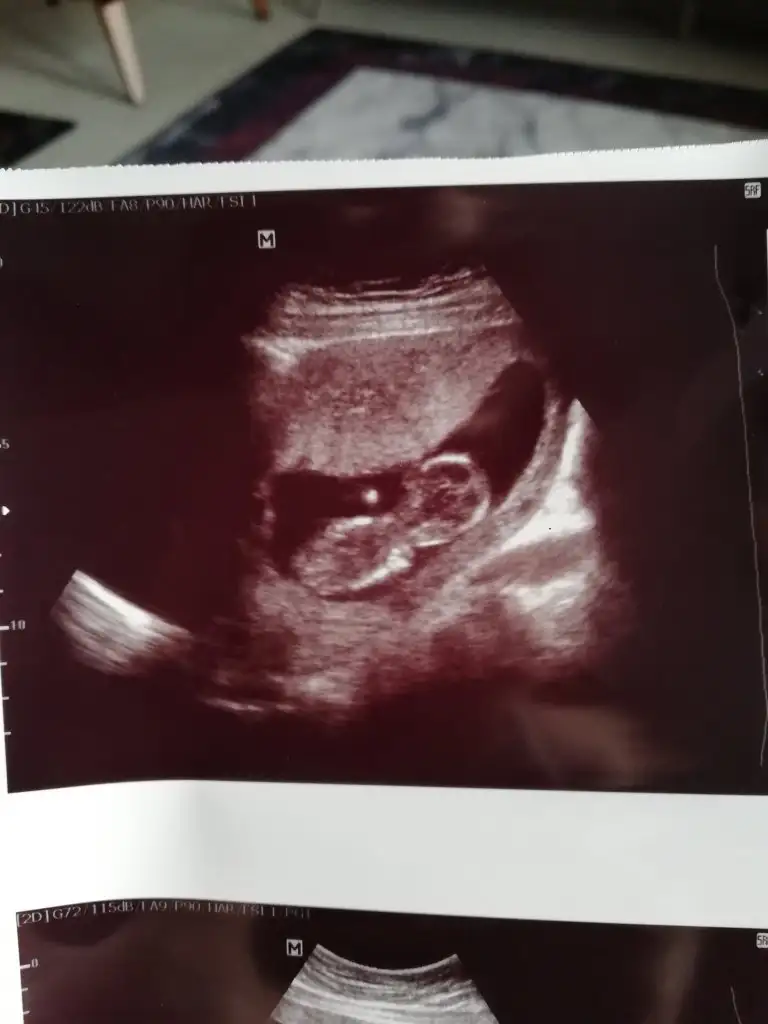

Sanki kız gibi eminde olamadım

Erkek gibi 12+ yada 13 hafta paylaşınIkra meyra yorumunuzu alabilir miyim![]()

Tmm o zaman kontrole gidersek paylaşırım inşallahErkek gibi 12+ yada 13 hafta paylaşın

![]()

11 12 13 haftalar nub için uygun şimdilik sanki erkek gibi gibi dediğimiz usgleri paylaşırmısınızIkra meyra bir bakarmısın canım

Şuan 19 haftalık kordon dolandığı için göremedi doktor cinsiyeti11 12 13 haftalar nub için uygun şimdilik sanki erkek gibi gibi dediğimiz usgleri paylaşırmısınız